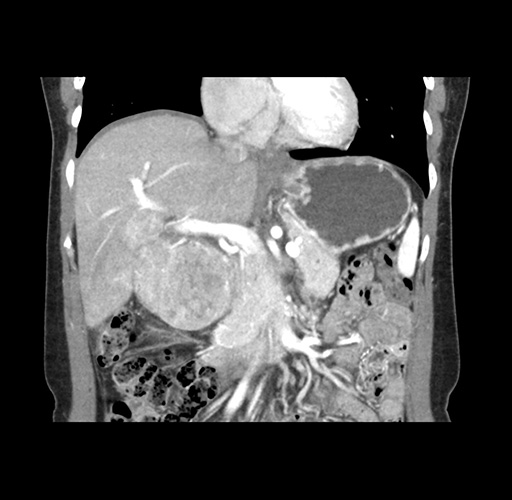

Imaging Analysis

Look through the patient's CT scan to identify any areas of concern for the necessary procedure.

Based on your CT findings, which issue(s) would give reason for "planned slowing down moment(s)" in this case?

Considering a standard left lateral sectionectomy procedure, what step(s) of the operation would you do differently in this case ?